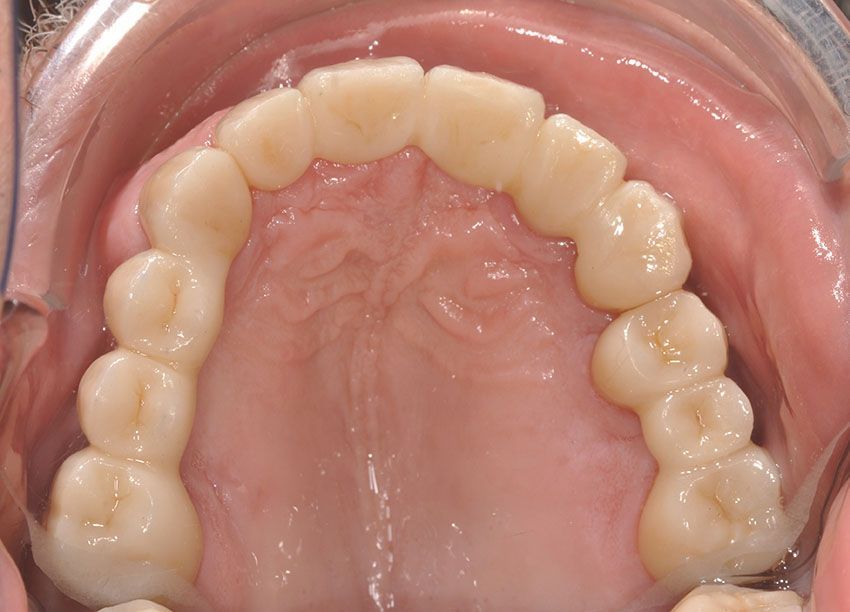

Diresti mai che è una protesi?

Il nostro obiettivo è restituire un sorriso naturale e armonioso attraverso protesi stabili ed integrate, ricorrendo alla protesi mobile solo quando non esistono alternative valide.

Ogni manufatto viene studiato sulla base delle caratteristiche del volto, del sorriso e dell’occlusione, per restituire funzionalità e comfort, esaudendo le aspettative estetiche di ogni paziente.

Le protesi fisse su impianti in particolare, offrono stabilità nel tempo, una resa estetica elevata, una sensazione naturale durante la masticazione, nonché l'integrazione ottimale con denti e tessuti. Il paziente viene accompagnato in ogni fase, dalla pianificazione alla finalizzazione del lavoro, con

pazienza, trasparenza e professionalità.